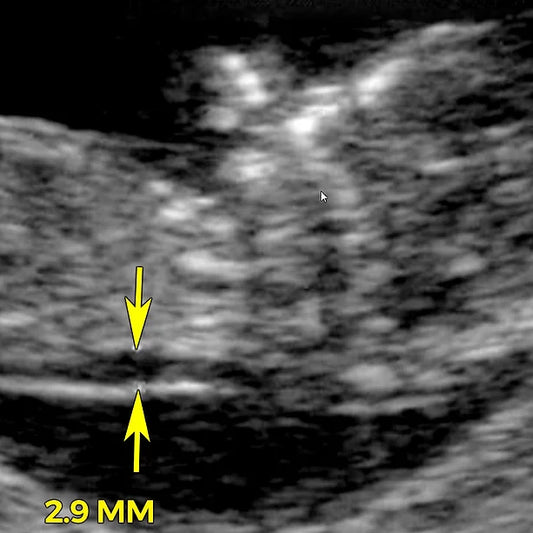

Nuchal translucency (NT) scan

Nuchal translucency (NT) is a collection of fluid under the skin at the back of your baby's neck. The amount of fluid is measured during an NT ultrasound scan: between...